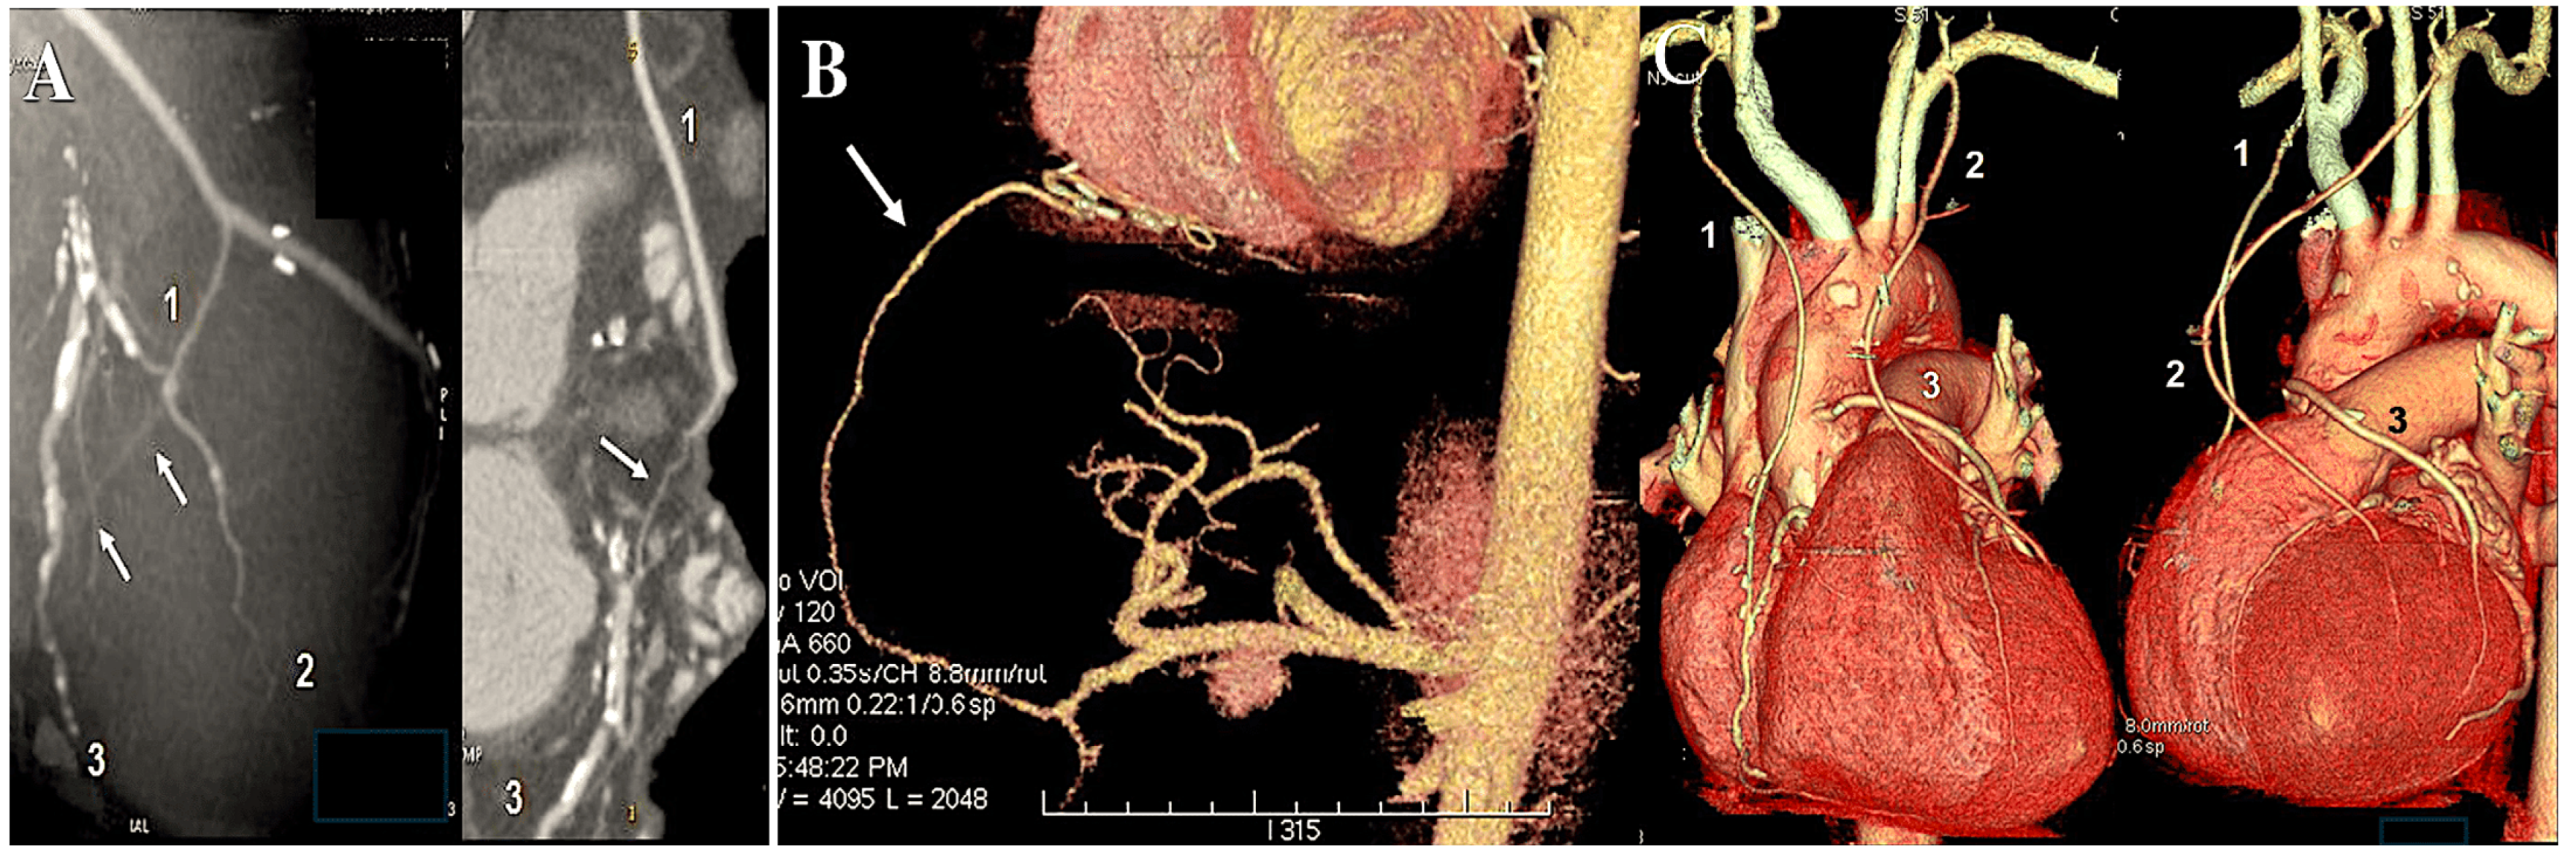

6. The Destiny of Radial Artery Grafts

Determinants of RA Patency